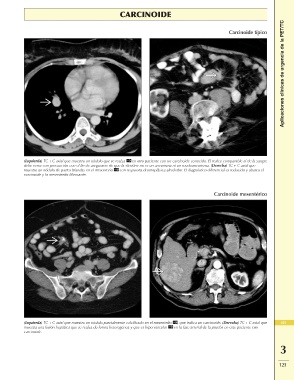

Carcinoide típico Aplicaciones clínicas de urgencia de la PET/TC

(Izquierda) TC + C axial que muestra un nódulo que se realza en otro paciente con un carcinoide conocido. El realce comparable al de la sangre

debe verse con precaución con el fin de asegurarse de que la «lesión» no es un aneurisma ni un seudoaneurisma. (Derecha) TC + C axial que

muestra un nódulo de partes blandas en el mesenterio con respuesta desmoplásica alrededor. El diagnóstico diferencial es reducido y abarca el

carcinoide y la mesenteritis fibrosante.

Carcinoide mesentérico

(Izquierda) TC + C axial que muestra un nódulo parcialmente calcificado en el mesenterio , que indica un carcinoide. (Derecha) TC + C axial que 419

muestra una lesión hepática que se realza de forma heterogénea y que es hipervascular en la fase arterial de la prueba en este paciente con

carcinoide. 3